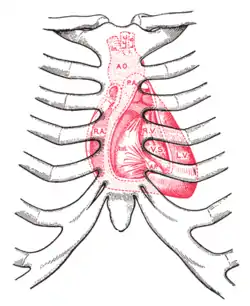

Surface anatomy

The aortic area, pulmonic area, tricuspid area and mitral area are areas on the surface of the chest where the heart is auscultated.[6] Heart sounds result from reverberation within the blood associated with the sudden block of flow reversal by the valves closing. Because of this, auscultation to determine function of a valve is usually not performed at the position of the valve, but at the position to where the sound waves reverberate.

| Aortic valve (to aorta) | right second intercostal space | upper right sternal border |

| Pulmonary valve (to pulmonary trunk) | left second intercostal space | upper left sternal border |

| Erb's point | Left third intercostal space | left sternal border |

| Tricuspid valve (to right ventricle) | left fourth, fifth intercostal spaces | lower left sternal border |

| Mitral valve (to left ventricle) | left fifth intercostal space | left midclavicular line |